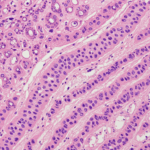

Vævsprøve (Biopsi)

Den endelige diagnose af brystkræft stilles ved at undersøge en vævsprøve fra det afficerede område under mikroskop. Der findes forskellige metoder til at tage en biopsi:

Grovnålsbiopsi (core needle biopsy)

Ved en grovnålsbiopsi bruges en tykkere nål til at udtage en eller flere små cylinderformede vævsprøver (cores). Dette giver mere væv til undersøgelse og er ofte den foretrukne metode til at diagnosticere brystkræft. Biopsien kan foretages under lokalbedøvelse og ofte under vejledning af ultralyd eller mammografi for at sikre, at nålen rammer det rigtige område.